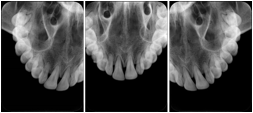

Intra-oral radiography typically involves acquisition of multiple images of various parts of the dentition. Many digital radiographic systems offer customized templates that are used for displaying the images in a study on the screen. These templates may also be referred to as mounts or view sets. The Structured Display Object represents a standard method of encoding and exchanging the layout and intended display of Structured Displays. A structured display object created in this manner could be stored with a study and exchanged with images to allow for complete reproduction of the original exam.

1. A patient visits a General Dentist where a Full Mouth Series Exam with 18 images is acquired. The dentist observes severe bone loss and refers the patient to a Periodontist. The 18 images from the Full Mouth Series along with a Structured Display are copied to a DICOM Interchange CD and sent with the patient to see the specialist. The Periodontist uses the CD to open the exam in his Dental Radiographic Software and consults via phone with the General Dentist. Both are able to observe the same exam showing the images on each user's display using the exact same layout.

Intra-oral Full Mouth Series Structured Display

Figure OO-1. Intra-oral Full Mouth Series Structured Display